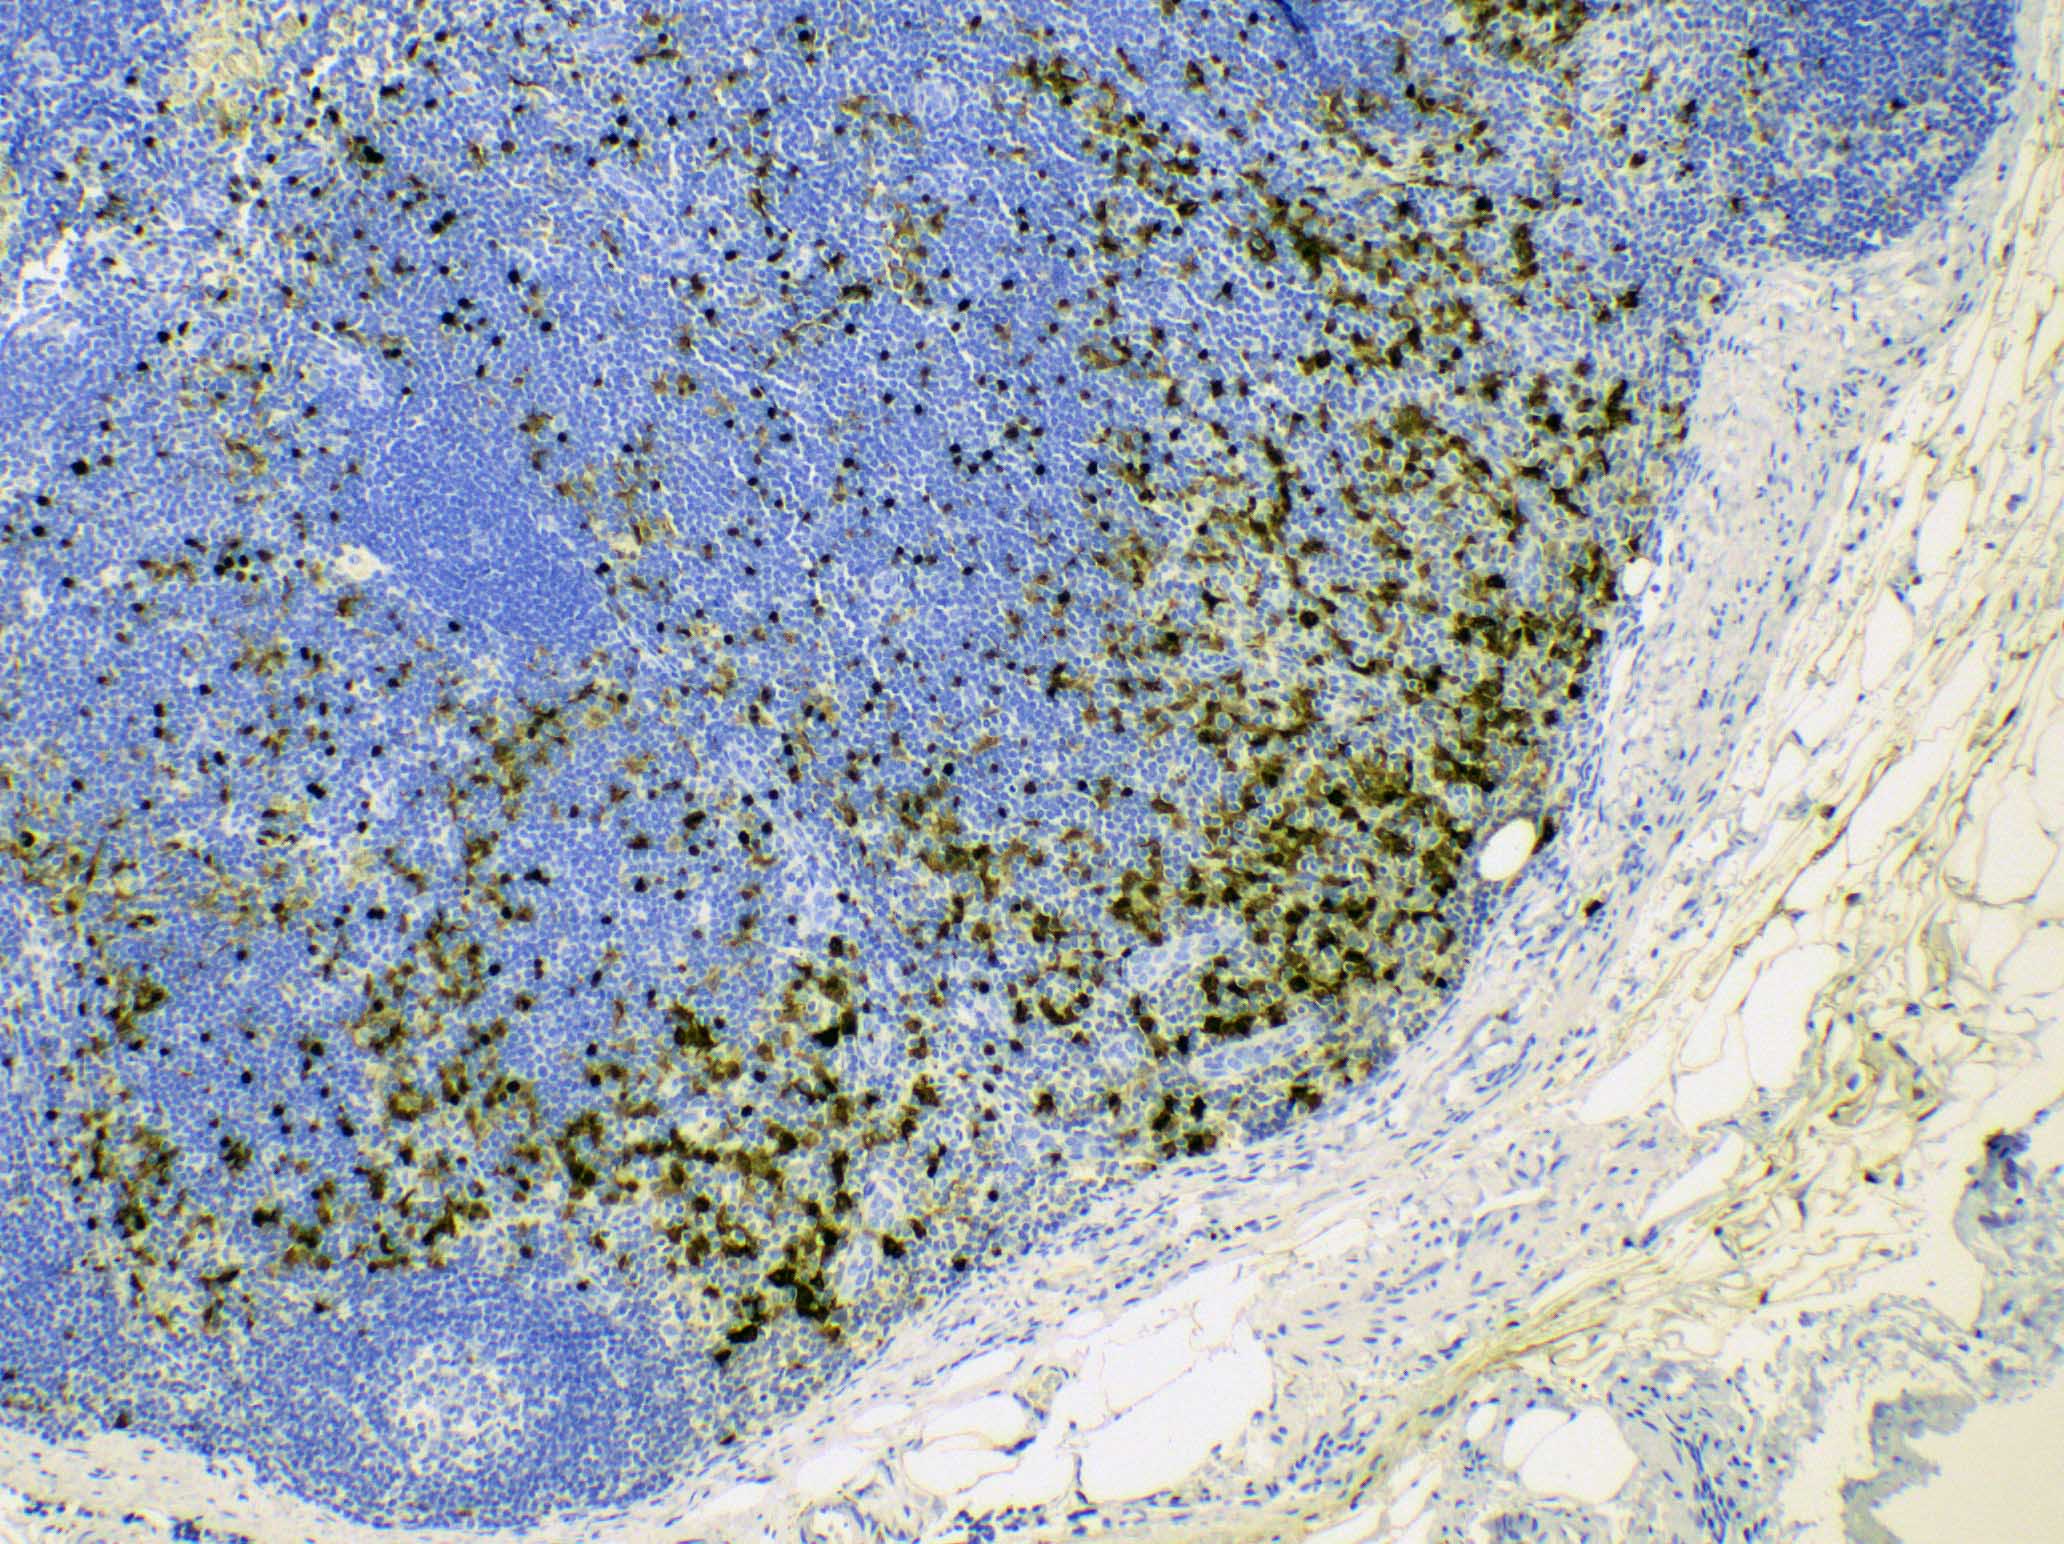

Microscopic (histologic) images

Contributed by Ingrid Tam, M.D., M.Sc., Emina Emilia Torlakovic, M.D., Ph.D. and Nikhil Sangle, M.D. (Case #396)

Positive stains

- S100, CD1a, CD207 / langerin: Langerhans cells

- CD4 and CD8: typically there is great predominance of CD4+ T cells over CD8

- S100, MUM1 / IRF4: interdigitating dendritic cells (Am J Surg Pathol 2022;46:1514)

- CD68: histiocytes and dendritic cells